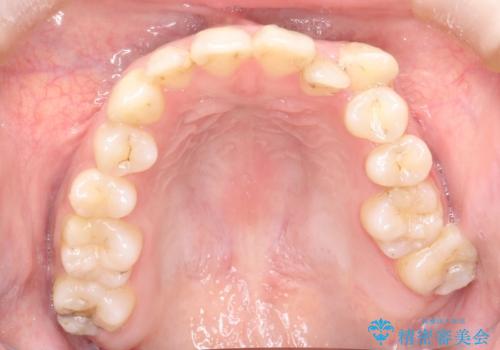

八重歯をインビザラインで非抜歯矯正

- 八重歯を主訴に来院されました。

インビザラインにて奥歯を後方に移動して八重歯が入るスペースを確保してく矯正する計画としました。

八重歯と前歯のガタガタがなくなり、歯並びがきれいになったのと、かみ合わせも改善することができました。